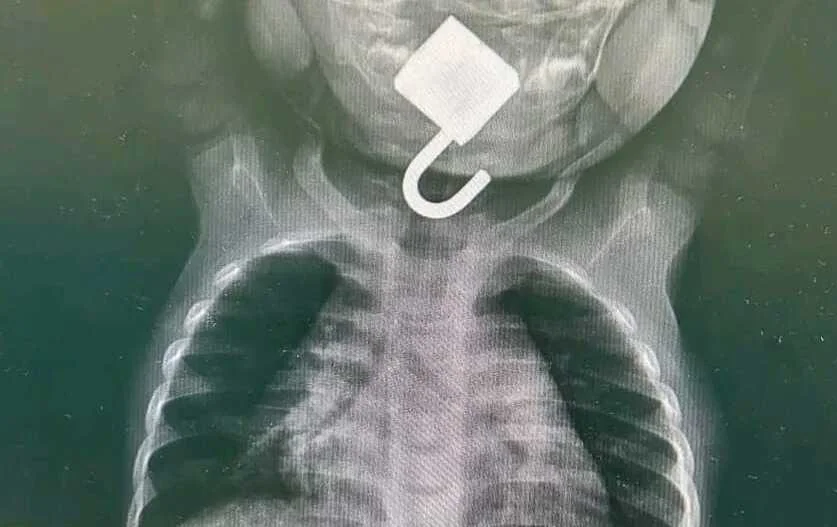

Após a chegada ao hospital, a equipa médica prontamente realizou exames de raio-X, que confirmaram a perigosa localização do cadeado na laringe da bebé.